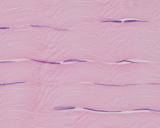

左図の腱組織:ピンクの横方向の蜜できれいなコラーゲンの中に、これを生産する線状の線維芽細胞が多数みられます。この線維芽細胞は非活動期です。